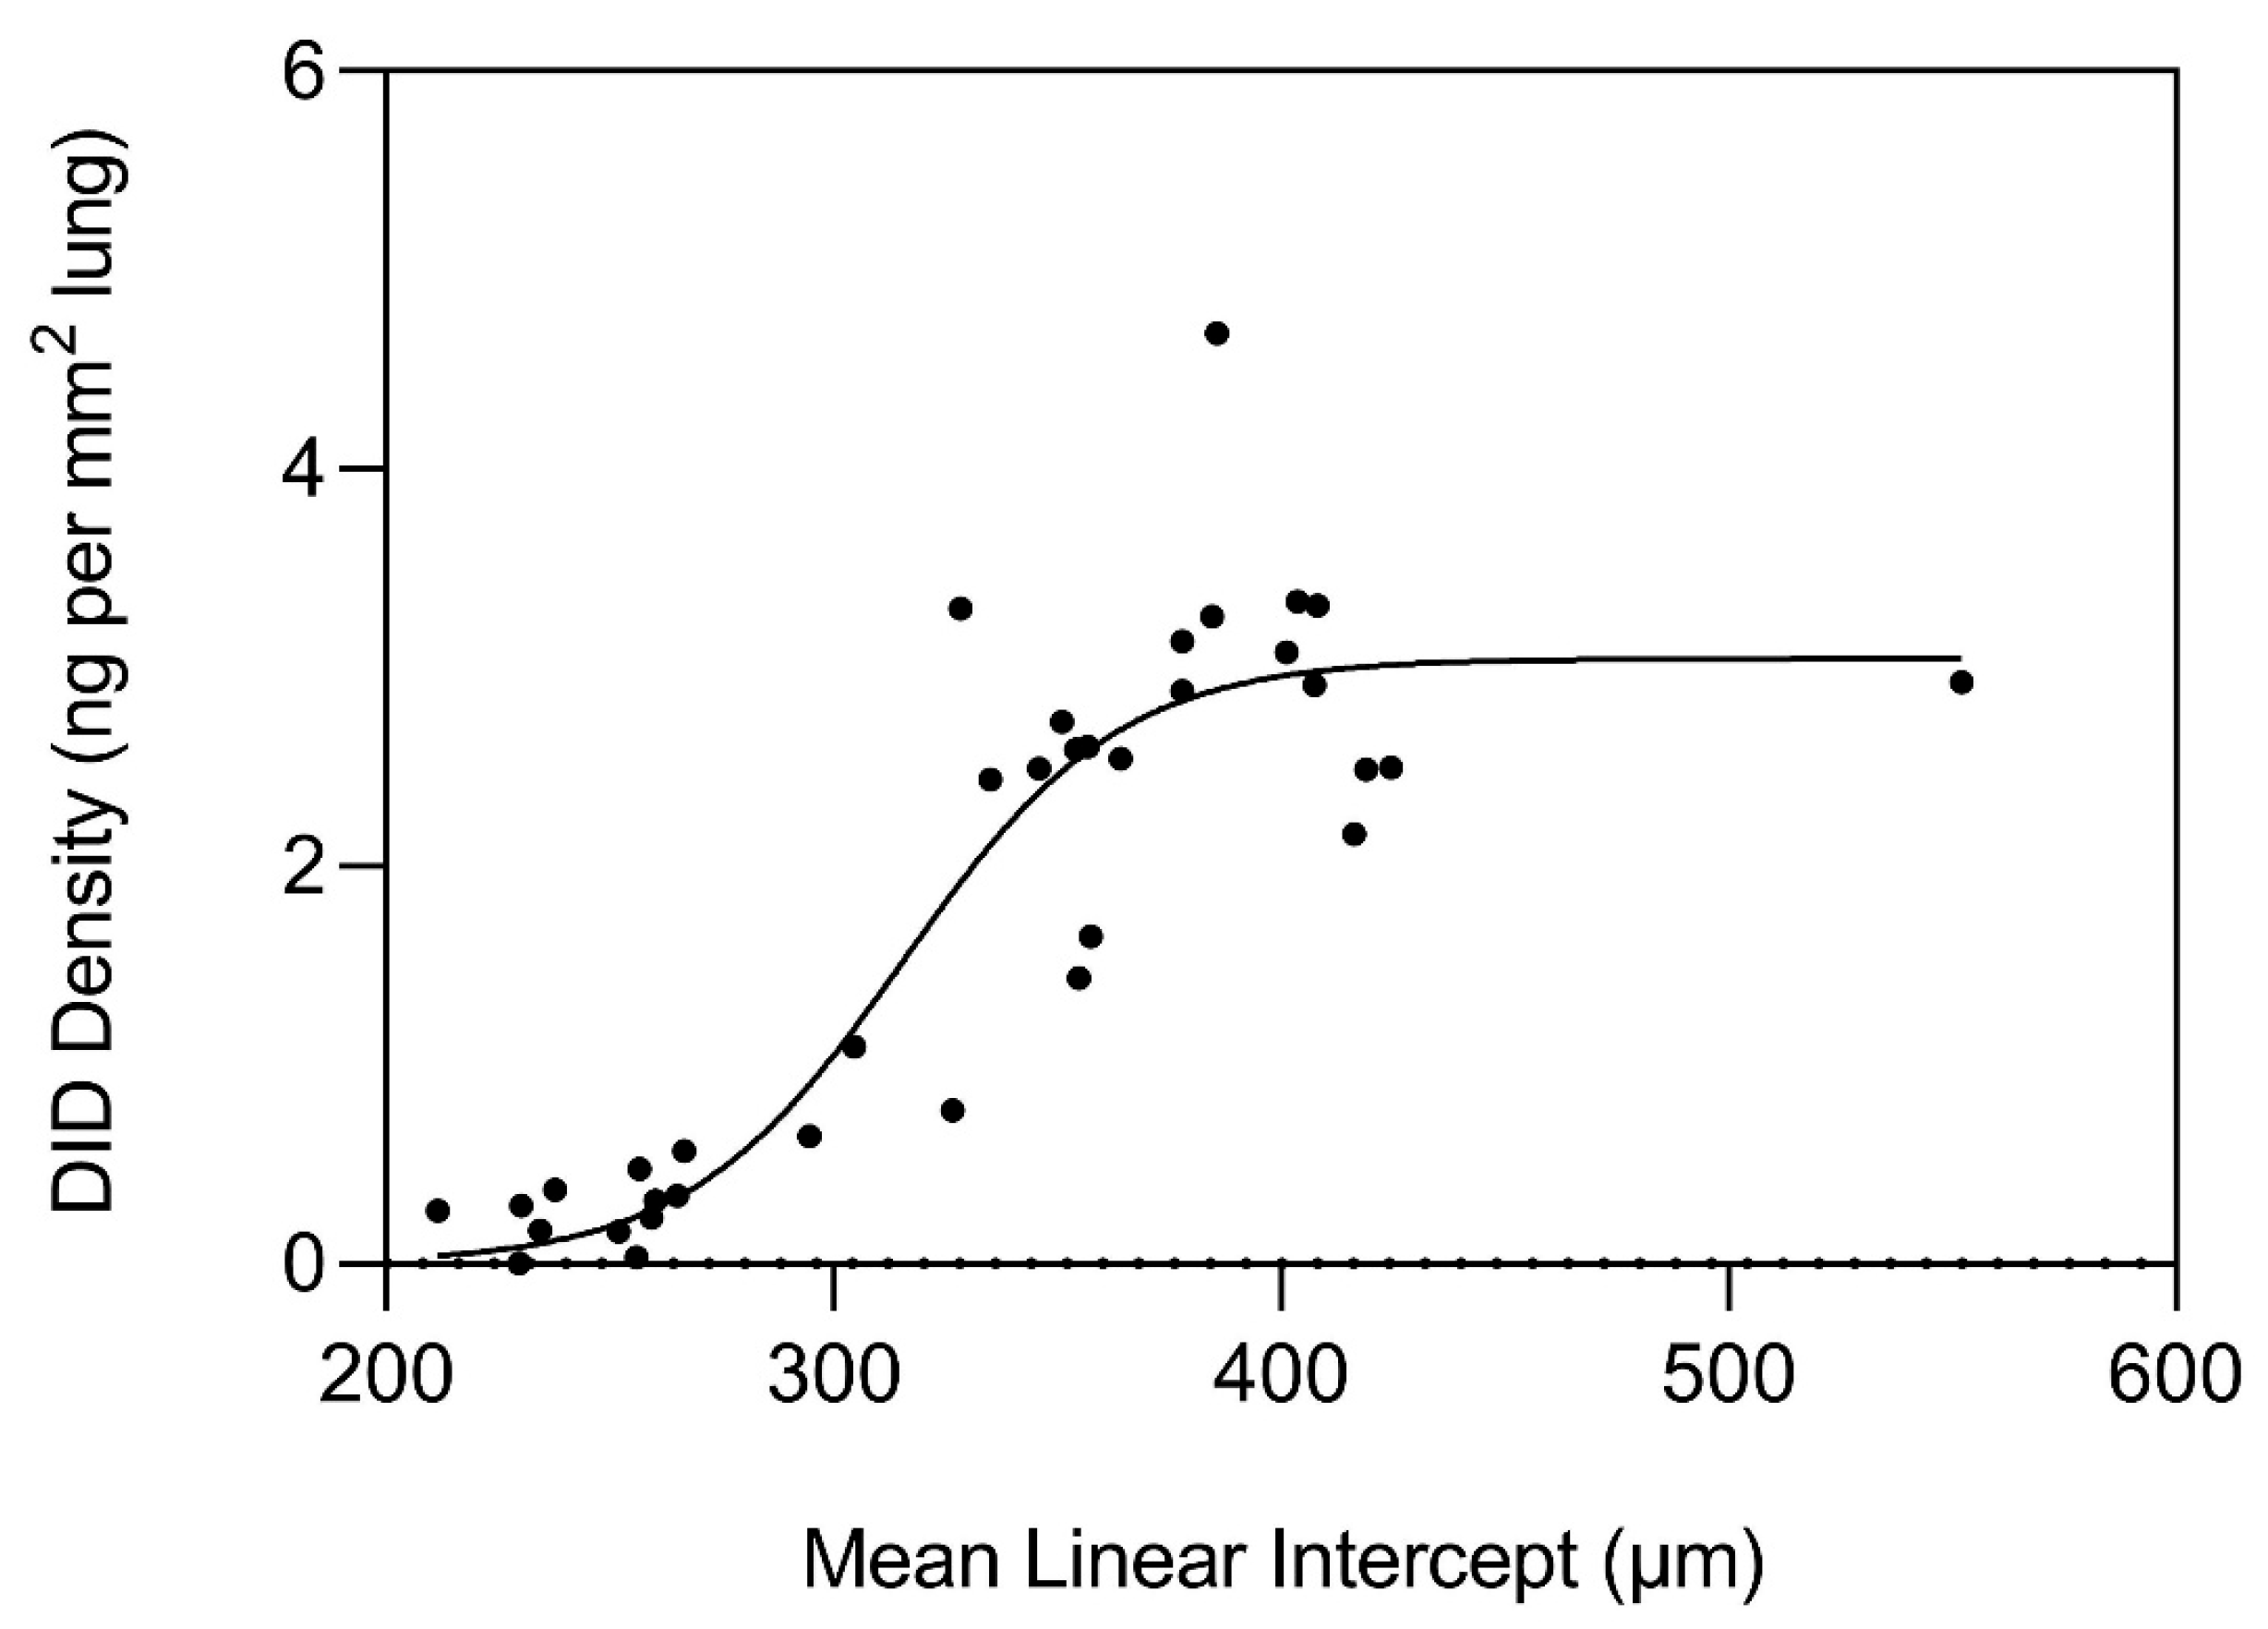

- Fagiola, M.; Reznik, S.; Riaz, M.; Qyang, Y.; Lee, S.; Avella, J.; Turino, G.; Cantor, J. The relationship between elastin cross linking and alveolar wall rupture in human pulmonary emphysema. Am. J. Physiol. Lung Cell Mol. Physiol. 2023, 324, L747–L755. [Google Scholar] [CrossRef] [PubMed]

- Cantor, J. Desmosine as a biomarker for the emergent properties of pulmonary emphysema. Front. Med. 2023, 10, 1322283. [Google Scholar] [CrossRef] [PubMed]